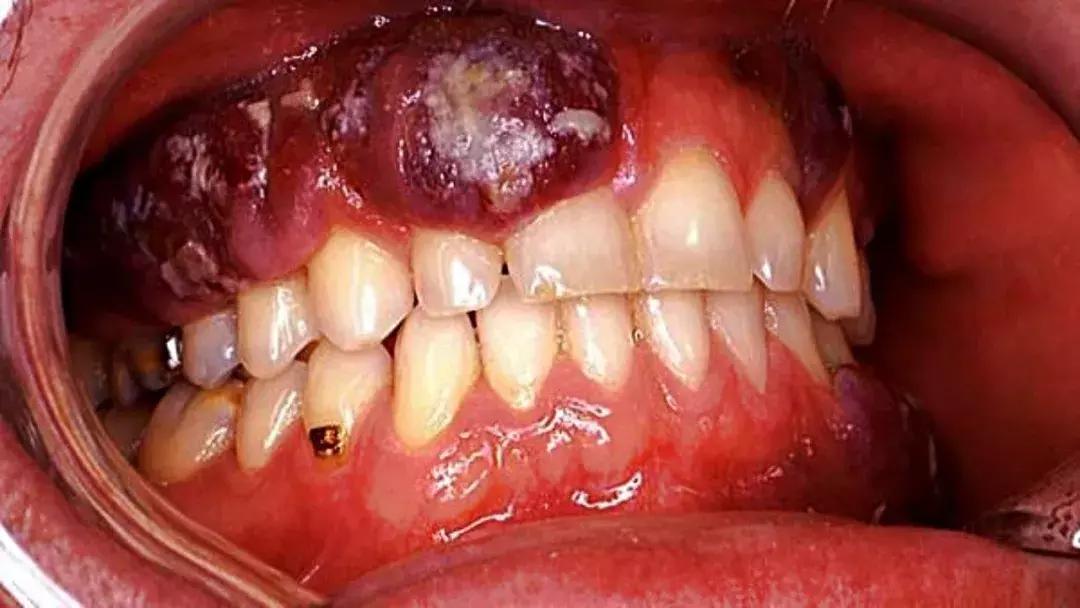

上图箭头指的部位为口腔黏膜纤维化;下图为病理切片

一项研究调查发现,爱好嚼槟榔的人中约有66%的人会不约而同地出现口腔黏膜病变,而在不嚼槟榔的人群中,这一概率仅为1.5%。另外,据不完全估计,湖南60%的口腔癌与嚼槟榔有关。

如果患者发展到OSF阶段,没有及时停止嚼槟榔,也没有进行正规治疗,那么口腔癌就近在咫尺了。

口腔癌

一旦OSF向口腔癌突变,情况将会变得越来越糟糕。如果是早期口腔癌,局部切除即可,如果拖到中晚期的话,不仅要切除舌头,还要做淋巴结清扫,影响外观是小,影响面部功能可就大了,万一还没结婚,就找不到对象了呢?是不是太不划算了?更可怕的是,超过半数以上的患者手术治疗后还会因为癌症复发而死。